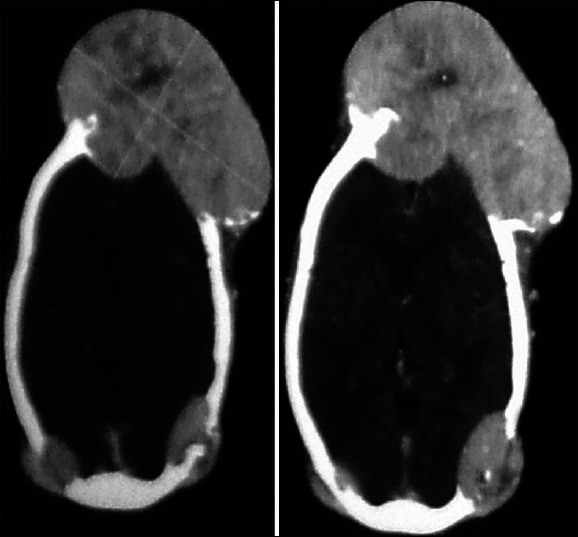

甲状腺滤泡癌是一种分化良好的甲状腺恶性肿瘤。本病生长缓慢,晚期易经血液途径向远处器官转移。肺和骨是两个最常见的转移部位。在大多数报道的滤泡性甲状腺癌转移到颅骨的病例中,转移发生在原发性癌症诊断和治疗很久之后。隐匿性滤泡性甲状腺癌表现为颅骨转移的病例很少报道。一位48岁的女性患者表现为颅骨额部大面积肿胀并伴有枕部肿胀。诊断证实为甲状腺滤泡癌多发性骨转移。如此大的转移灶是非常罕见的。我们报告一例转移性滤泡性甲状腺癌在我们的机构表现为巨大的颅骨肿瘤。

Follicular carcinoma of thyroid is a well differentiated thyroid malignancy. It is slow growing in nature and tends to metastasize to remote organs in advanced stage by hematogenous route. Lung and bone are the two most common sites of metastasis. In most of the reported cases of follicular thyroid carcinoma metastasizing to the skull, metastases occurred long after the diagnosis and institution of treatment for primary cancer. Very few cases have been reported with occult follicular thyroid carcinoma presenting as skull metastasis. A 48-year-old female patient presented with massive swelling in the frontal region of skull associated with swellings in occipital region. Evaluation confirmed that it is multiple metastases to skull bones from follicular thyroid carcinoma. This is a very rare presentation with such a large size of metastasis. We report this case of a metastatic follicular thyroid carcinoma presenting as massive skull tumor at our institution.